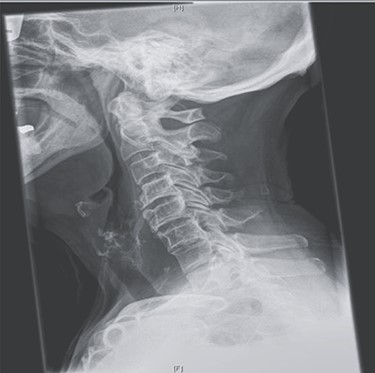

Her past history included right knee joint arthroplasty. There were no neurological manifestations, and there was no history of neck pain or trauma. The findings on physical examination were unremarkable. The routine blood test results were within the normal range. Oesophagoscopy revealed luminal stenosis by external compression on the posterior hypopharynx/oesophageal wall with no tumour or diverticula. Lateral neck X-ray and computed tomography (CT) examinations showed a giant anterior multilevel osteophytic formation spanning C4/5/6 and compressing the oesophagus, with no ossification of the anterior longitudinal ligament (Fig. 1A). A gastrografin swallow showed that osteophytes were severely protruding and impinging on the oesophagus, with partial obstruction (Fig. 1B).

(A) Lateral X-ray reveals giant multilevel osteophytes at C4/5/6 compressing the oesophagus; (B) a gastrografin swallow showed that osteophytes were severely protruding impinging on the oesophagus with partial obstruction.